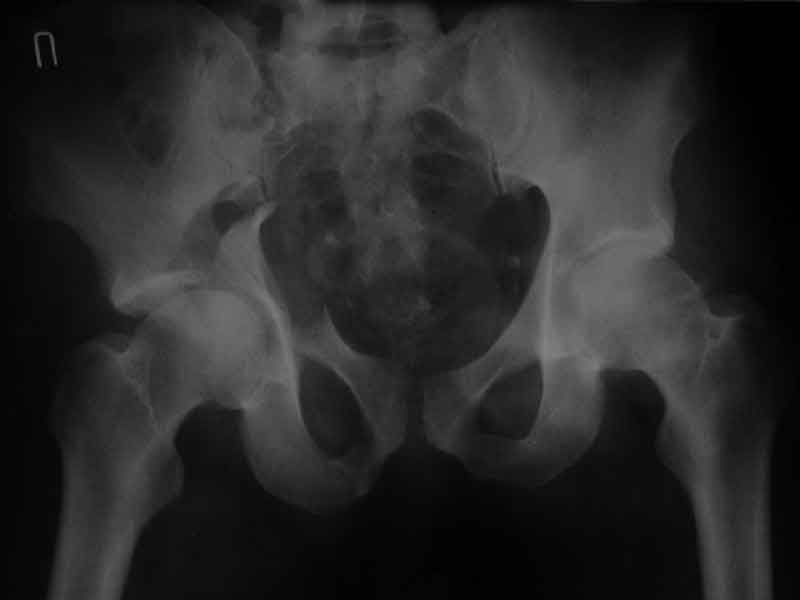

еще одно дополнение

Дополнение, минимальный набор необходимых прекций, необходимых для лечения повреждений вертлужной впадины

Фас. Inlet

Подвздошная Запирательная